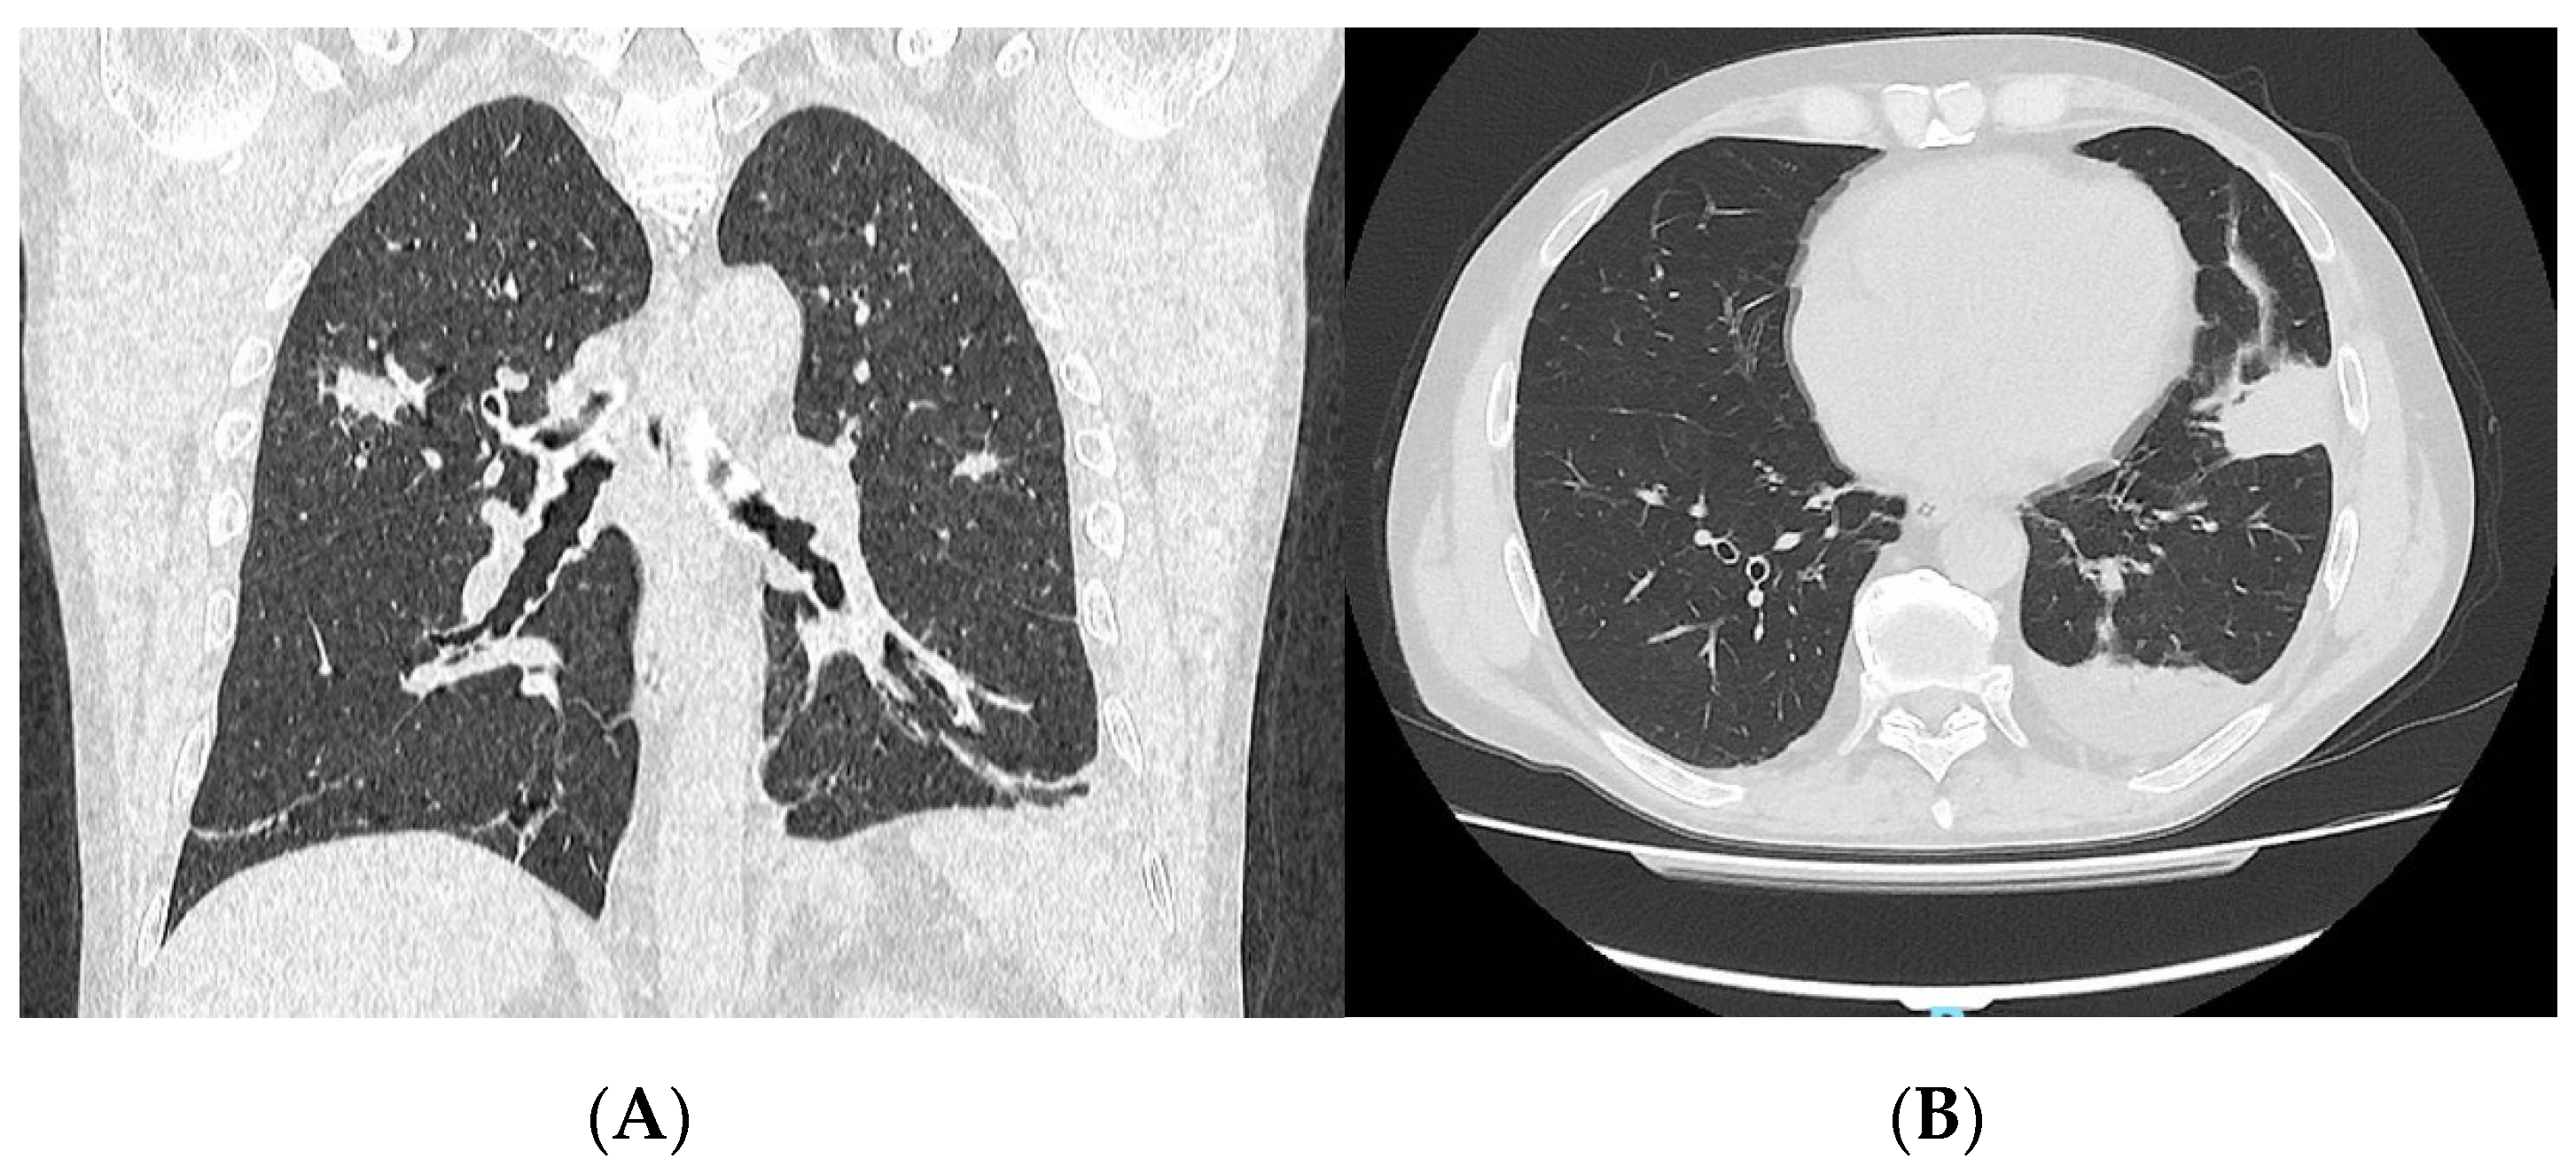

3.2. Case N. #2

| 24. Our patient #2 | 68 | M | Asthma, CRSwNP with nasal septal perforation | Eosinophilia (up to 1160/μL) MPO-ANCA: + PR3-ANCA: - | Inhaled CS/LABA/LAMA OCS Montelukast Benralizumab | General symptoms (fever, weakness, weight loss, arthralgias), bilateral conjunctival hyperaemia and crusty rhinitis | AEC: 11,540/µL CRP: 137 mg/L MPO-ANCA: + (67 IU/mL) IgE: 81.6 IU/mL | 6 | Yes | OCS (25 mg/d) Mepolizumab (100 mg/4w) |